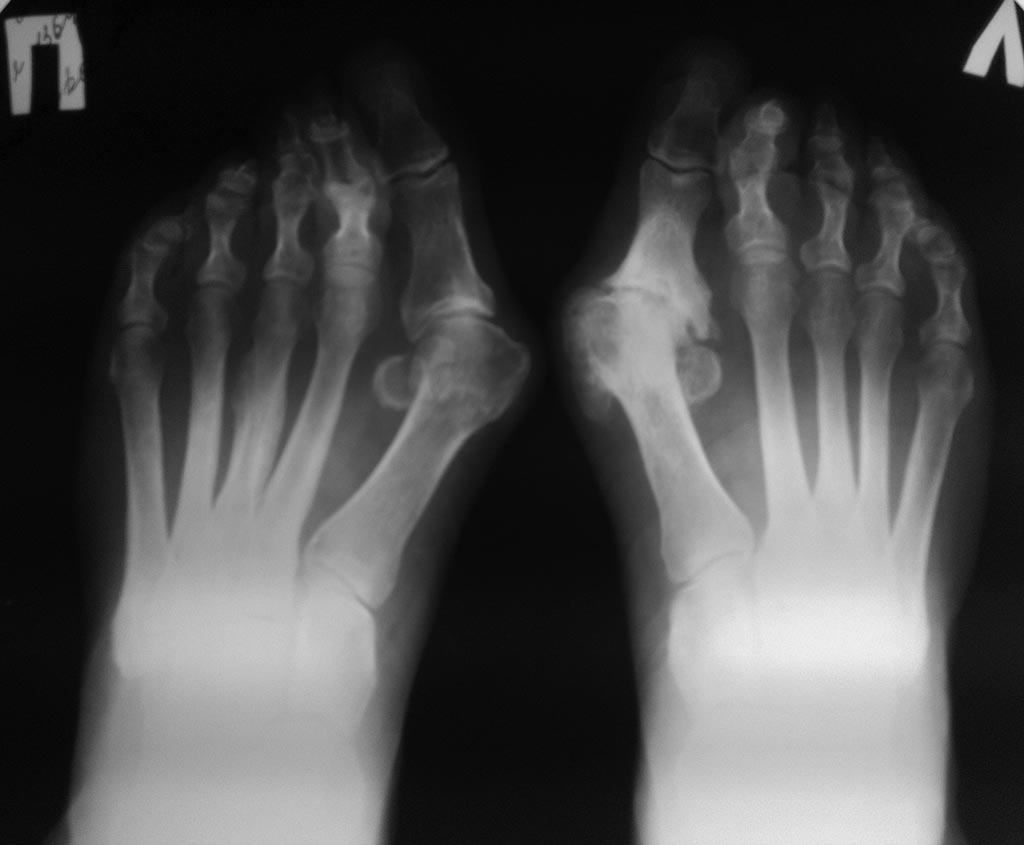

Женщина 60 лет,имеет деформацию пеереднего отдела обеих стоп в виде Hallux valgus, молоткообразной деформации вторых пальцев, артроза первых плюсне-фаланговых и других суставов.

Каков может быть объем коррекции стоп, с учетом артроза слева?

Кроме hallux valgus и артроза первого плюснефалангового сустава левой стопы на снимках мы видим значительное преобладание длин 2-4 плюсневых костей над длиной первой плюсневой. Значит головки центральных плюсневых костей подвергаются перегрузке, которая, вероятно, раньше уже проявилась маршевым переломом (или была травма?) третьей плюсневой на правой стопе (сейчас уже сросшимся). По идее должны быть натоптыши на подошве, о которых Вы не пишете. Даже если нет натоптышей, такую избыточную длину нужно учитывать во время операции. С первым плюснефаланговым суставом левой стопы понятно - лучше всего сделать артродез, одновременно устранив отклонение пальца кнаружи. А на правой стопе никакого особенного артроза нет. Можно сделать любую операцию, которой вы владеете, по устранению hallux valgus. Например, шевронную остеотомию: первый межплюсневый угол тут маленький и этой относительно мало травматичной операции вполне будет достаточно. Если при этом полностью не устранится отклонение первого пальца - дополнить операцию остеотомией основания основной фаланги. Что же касается латеральных лучей, я бы советовал выполнить остеотомию по Вейль 2-4 плюсневых. Ее можно фиксировать винтами, а можно и не фиксировать. Как Вам больше нравится. Остаются вторые пальцы. Нужно быть очень уверенным в себе хирургом, чтобы думать о резекционной артропластике на таком красном, воспаленном пальце, как на левой стопе. Да и на правой. Конечно, наилучшее решение в такой ситуации - чрескожная операция. Можно сделать похожую на чрескожную операцию: при выполнении остеотомии плюсневых костей удлинить разгибатели пальцев и из этого же доступа микропилой пересечь основание основной фаланги 2 пальца. Можно под углом, чтобы добиться большего укорочения. Фиксировать ничем, кроме повязки, не нужно. Но повязка должна быть наложена качественно, с фиксацией по отдельности каждого пальца. А если контрактура проксимального межфалангового сустава фиксированная (об этом Вы тоже не пишете), можно самым узким скальпелем через подошвенный прокол пересечь и сухожилия сгибатели. В любом случае нужно постараться избежать вмешательства на проксимальном межфаланговом суставе и внутренней фиксации пальца.